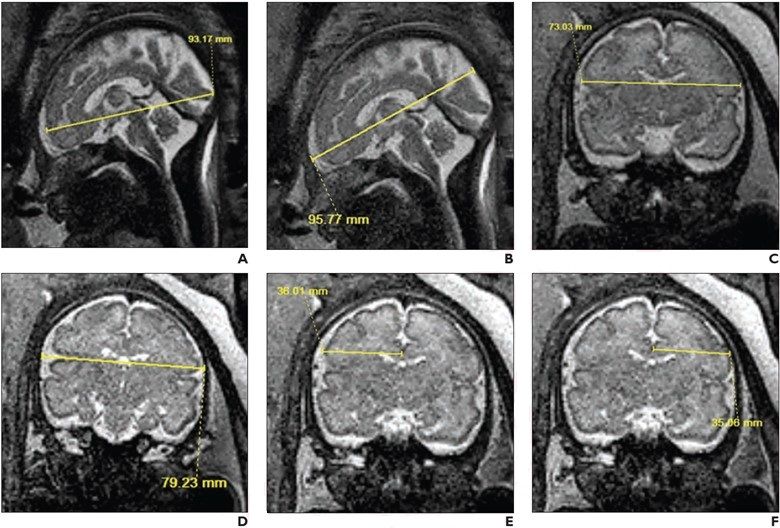

Incorporating artificial intelligence (AI)-based technology, Neosoma HGG reportedly demonstrated a 95.5 percent accuracy rate in measuring brain tumor volume on brain magnetic resonance imaging (MRI) scans at various points during the treatment of patients with high-grade gliomas.